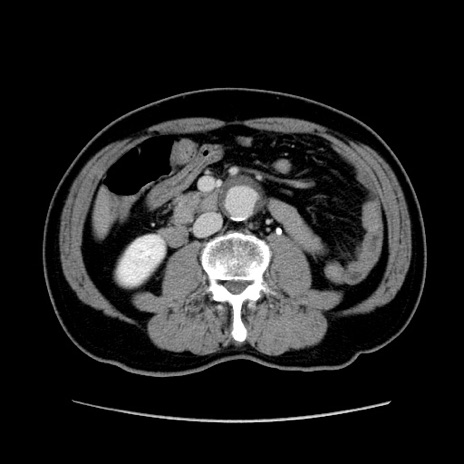

症例34(横断像)

【症例】60歳代 男性

【主訴】右鼠径部膨隆

【現病歴】1年程前より右鼠径部膨隆あり。自己にて還納可能だったため放置していた。3時間前より右鼠径部の脱出を認め、還納困難となり受診。

【身体所見】右鼠径部に小児頭大の膨隆あり。弾性硬であり、用手還納は困難。左鼠径部にも膨隆を認める。脱出はなし。